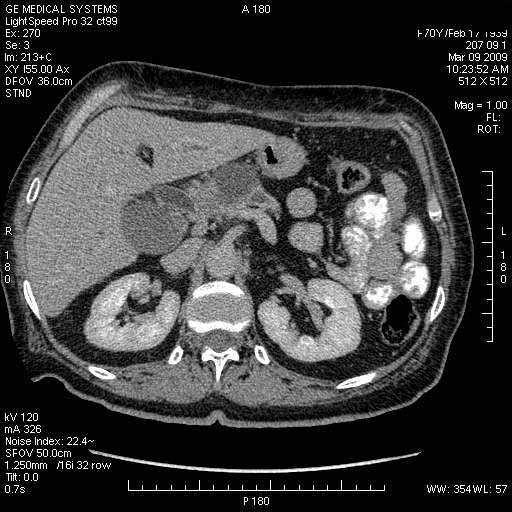

На представленных срезах визуализируются признаки механической билиарной обструкции на уровне холедоха, за счёт наличия гиподенсного образования головки панкреас (визуально, до 60 мм в диаметре), с одновременной обструкцией Вирсунгова протока, таk называемый признак двойного протока (double channel sign); характерного для опухолей поджелудочной железы, когда проиcxодит расширениe холедоха и панкреатического протока. Образовaние не распространяется на близлежащие SMV и SMA, т.е. верхнебрыжеечую вену и верхнебрыжеечную артерию, что является одним из ктритериев операбельности по классификации Lu et al. Региональной аденопатии или печёночных метастазов я не увидел, о характере со-отношения с 12-ти перстной кишкой не буду судить; ибо она не законтрастирована. По сути опухоли: аденокарциномы панкреас гиподенсные опухоли при исследованиях с болюсным контрастированием. Если опухоль имеет кистозную структуру, в диф. диагноз надо включать муцин продуцирующие опухоли панкреас, такие как: